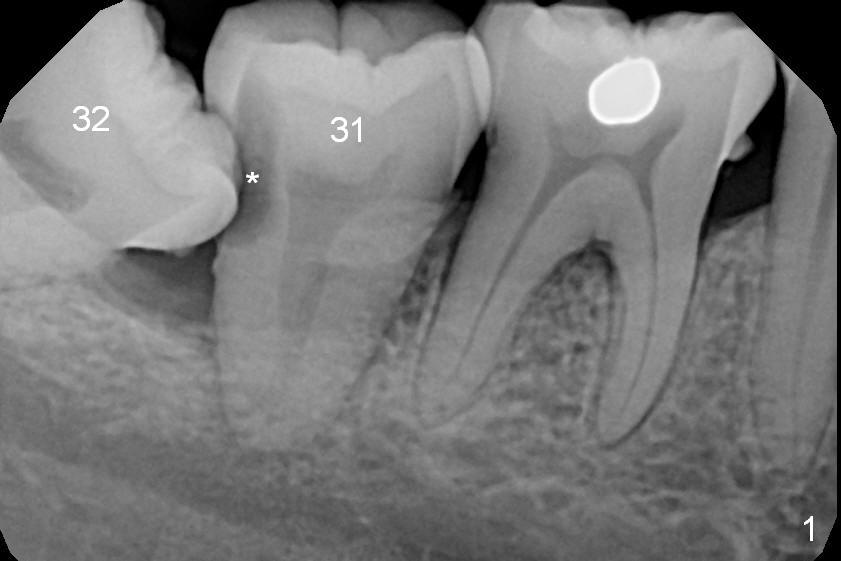

A 39-year-old woman has pain and mobility associated with the tooth #31 (Fig.1 (taken 5 months earlier), 2). It is easy to extract the mesioangularly impacted third molar (#32) after extraction of #31. After debridement and Clindamycin socket disinfection, collagen plug is placed in #32 socket, while allograft in the bottom half of the #31 one. The most coronal portion of the sockets are packed with mixture of collagen and Osteogen plugs and fixed in place with 4-0 Chromic gut (Fig.3). Two or 3 months postop, use #15 to start bone expansion at #31, followed by osteotomes or bone expanders and Tatum tapered taps. Take preop X-ray for depth measurement. The socket is close to the Inferior Alveolar Canal. In one word, no drill will be used for osteotomy. Place bone graft (Fig.4 red circles) prior to implant placement (white outline). Take CT post implant placement to confirm that the Inferior Alveolar Nerve is lingual to the implant.